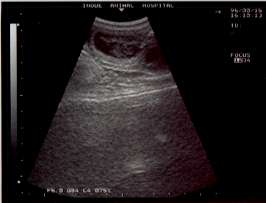

診察台にあがりエコーをあてたところ

「いるね、これは!」という先生の言葉。

先生がエコーの画像を見ながら説明してくれたのだが、

素人のわたしにはどれが子供なのかまったくわからない。

子宮の中にもやもやした物があるなくらいはわかったのだが・・・・。(笑)

でも2匹以上は確実にいるとのこと。